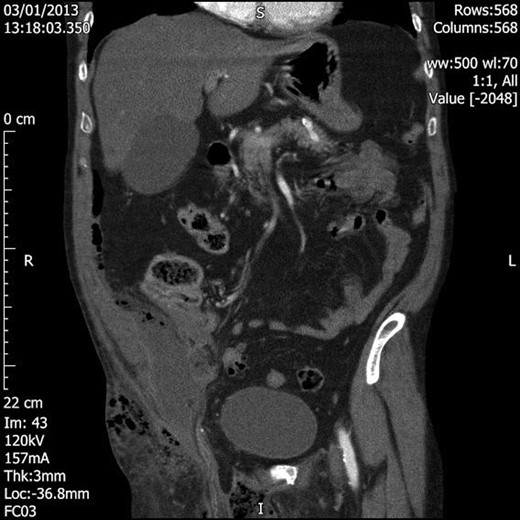

Blood tests showed grossly elevated white cell count and acute kidney injury, along with markedly deranged clotting parameters (Table 1). The patient was resuscitated with further intravenous fluids, and broad-spectrum antibiotics were commenced. Prothrombin complex concentrate was administered to correct the international normalized ratio. En route to theatre for surgical debridement the patient underwent computed tomography (CT) to assess for intra-abdominal sepsis, given the clinical findings of lower abdominal peritonism and the recent reported lower abdominal pain. This revealed a large amount of loculated gas mainly within the right hemiscrotum with superior extension into the inguinal canal, lower anterior abdominal wall and subcutaneous soft tissue, and lateral extension towards the right buttock; along the right lateral pelvic wall, there was a 10 × 4 × 6 cm collection containing fluid and air. No bowel loops were identified extending into the inguinal region (Figs 1 and 2).

Coronal section CT image demonstrating extension of the loculated air superiorly into the inguinal canal and lower anterior abdominal wall and laterally into the right buttock. There is also a 10 × 4 × 6 cm fluid and air collection in the right pelvis.